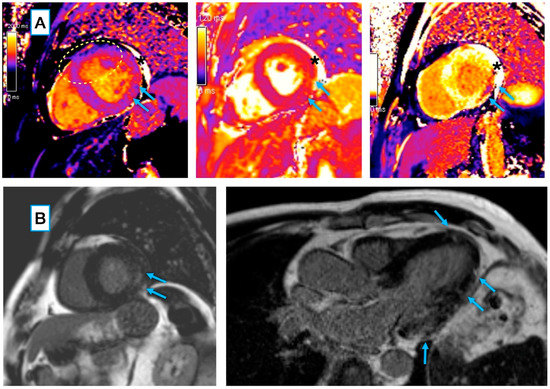

3.3.1. Conventional and LGE Sequences

3.3.2. Mapping Sequences

- Wojtowicz, D.; Dorniak, K.; Ławrynowicz, M.; Rejszel-Baranowska, J.; Fijałkowska, J.; Kulawiak-Gałąska, D.; Szurowska, E.; Koziński, M. Spectrum of lesions visualized in cardiac magnetic resonance imaging in COVID-19-related myocarditis: Findings from a pilot study of the TRICITY-CMR trial. Cardiol. J. 2021, 28, 976–978. [Google Scholar] [CrossRef]